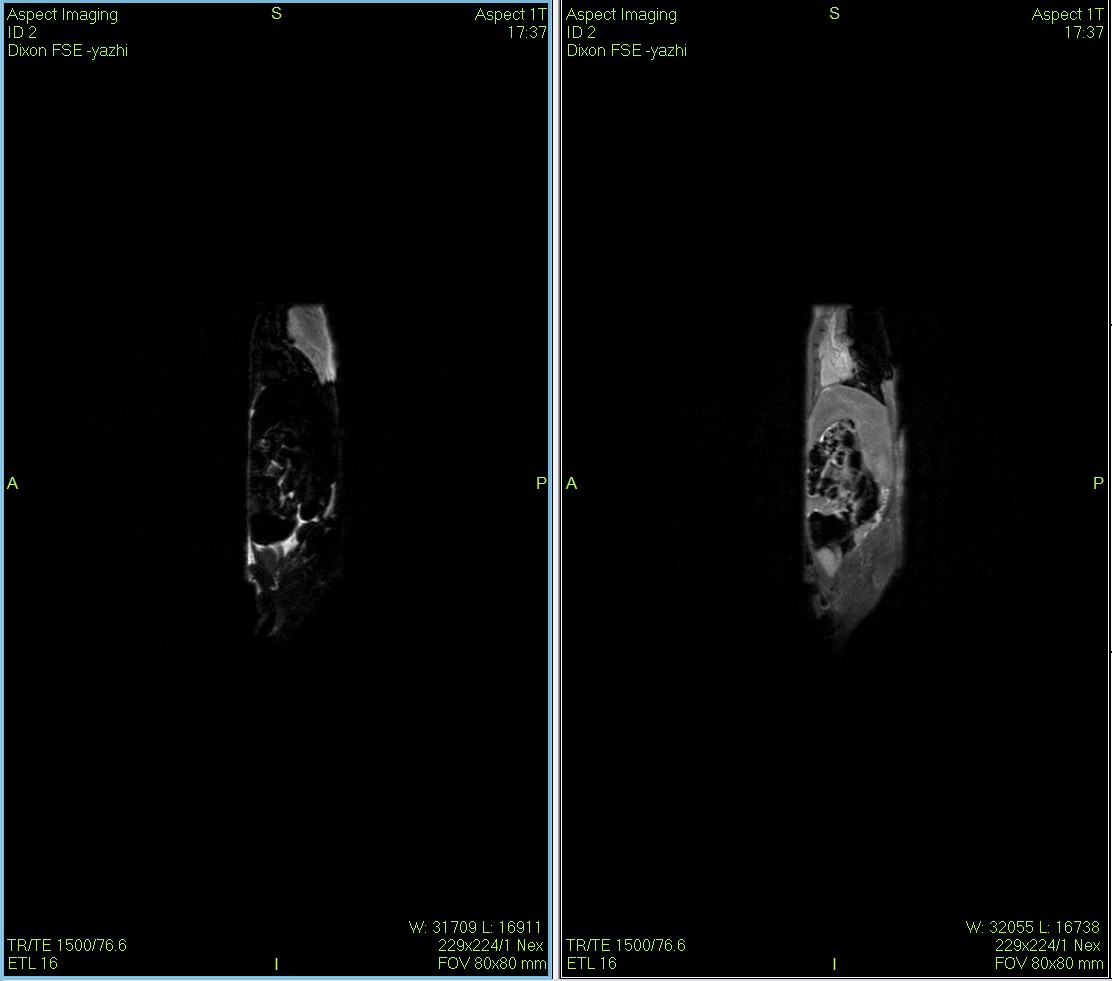

Dixon序列用于大鼠、小鼠水脂分离磁共振成像-脂肪抑制技术

Dixon脂肪抑制技术是由Dixon 提出,其基本原理是利用水、脂肪的化学位移差异,使用不同的回波时问,分别采集水和脂肪质子的in Phase 和 opposed -phase两种回波信号。

低场核磁共振技术,已被广泛应用于小动物(大、小鼠)实验模型中,用于监测体内脂肪分布及沉积情况。这不仅有助于揭示人类肥胖代谢性疾病的病因,还为肥胖治疗药物的评价提供了重要依据。通过低场核磁共振技术结果表征,科研工作者能够直观地观察到小鼠体内脂肪的变化,从而更深入地理解肥胖症的发病机制。